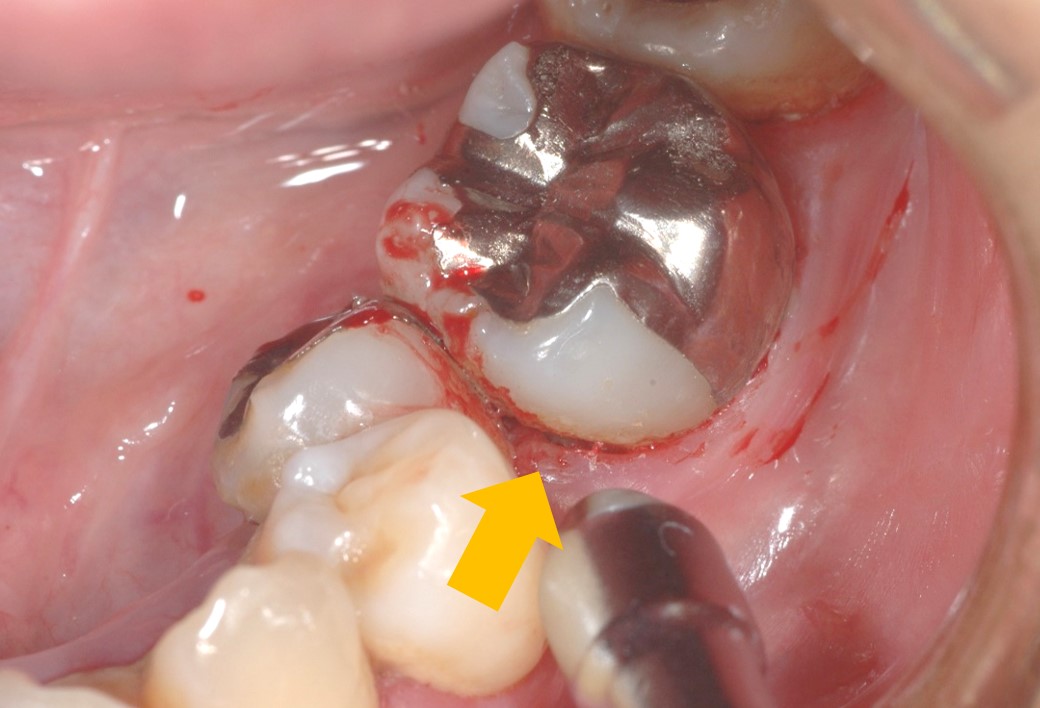

また、このプラークのせいで歯肉に炎症が起きます。下はこの部分にエアー(風)をかけた瞬間の写真です。歯と歯肉の境目が開いているのが分かるでしょうか?さらに炎症を起こしているのでエアーをかけただけで出血します。